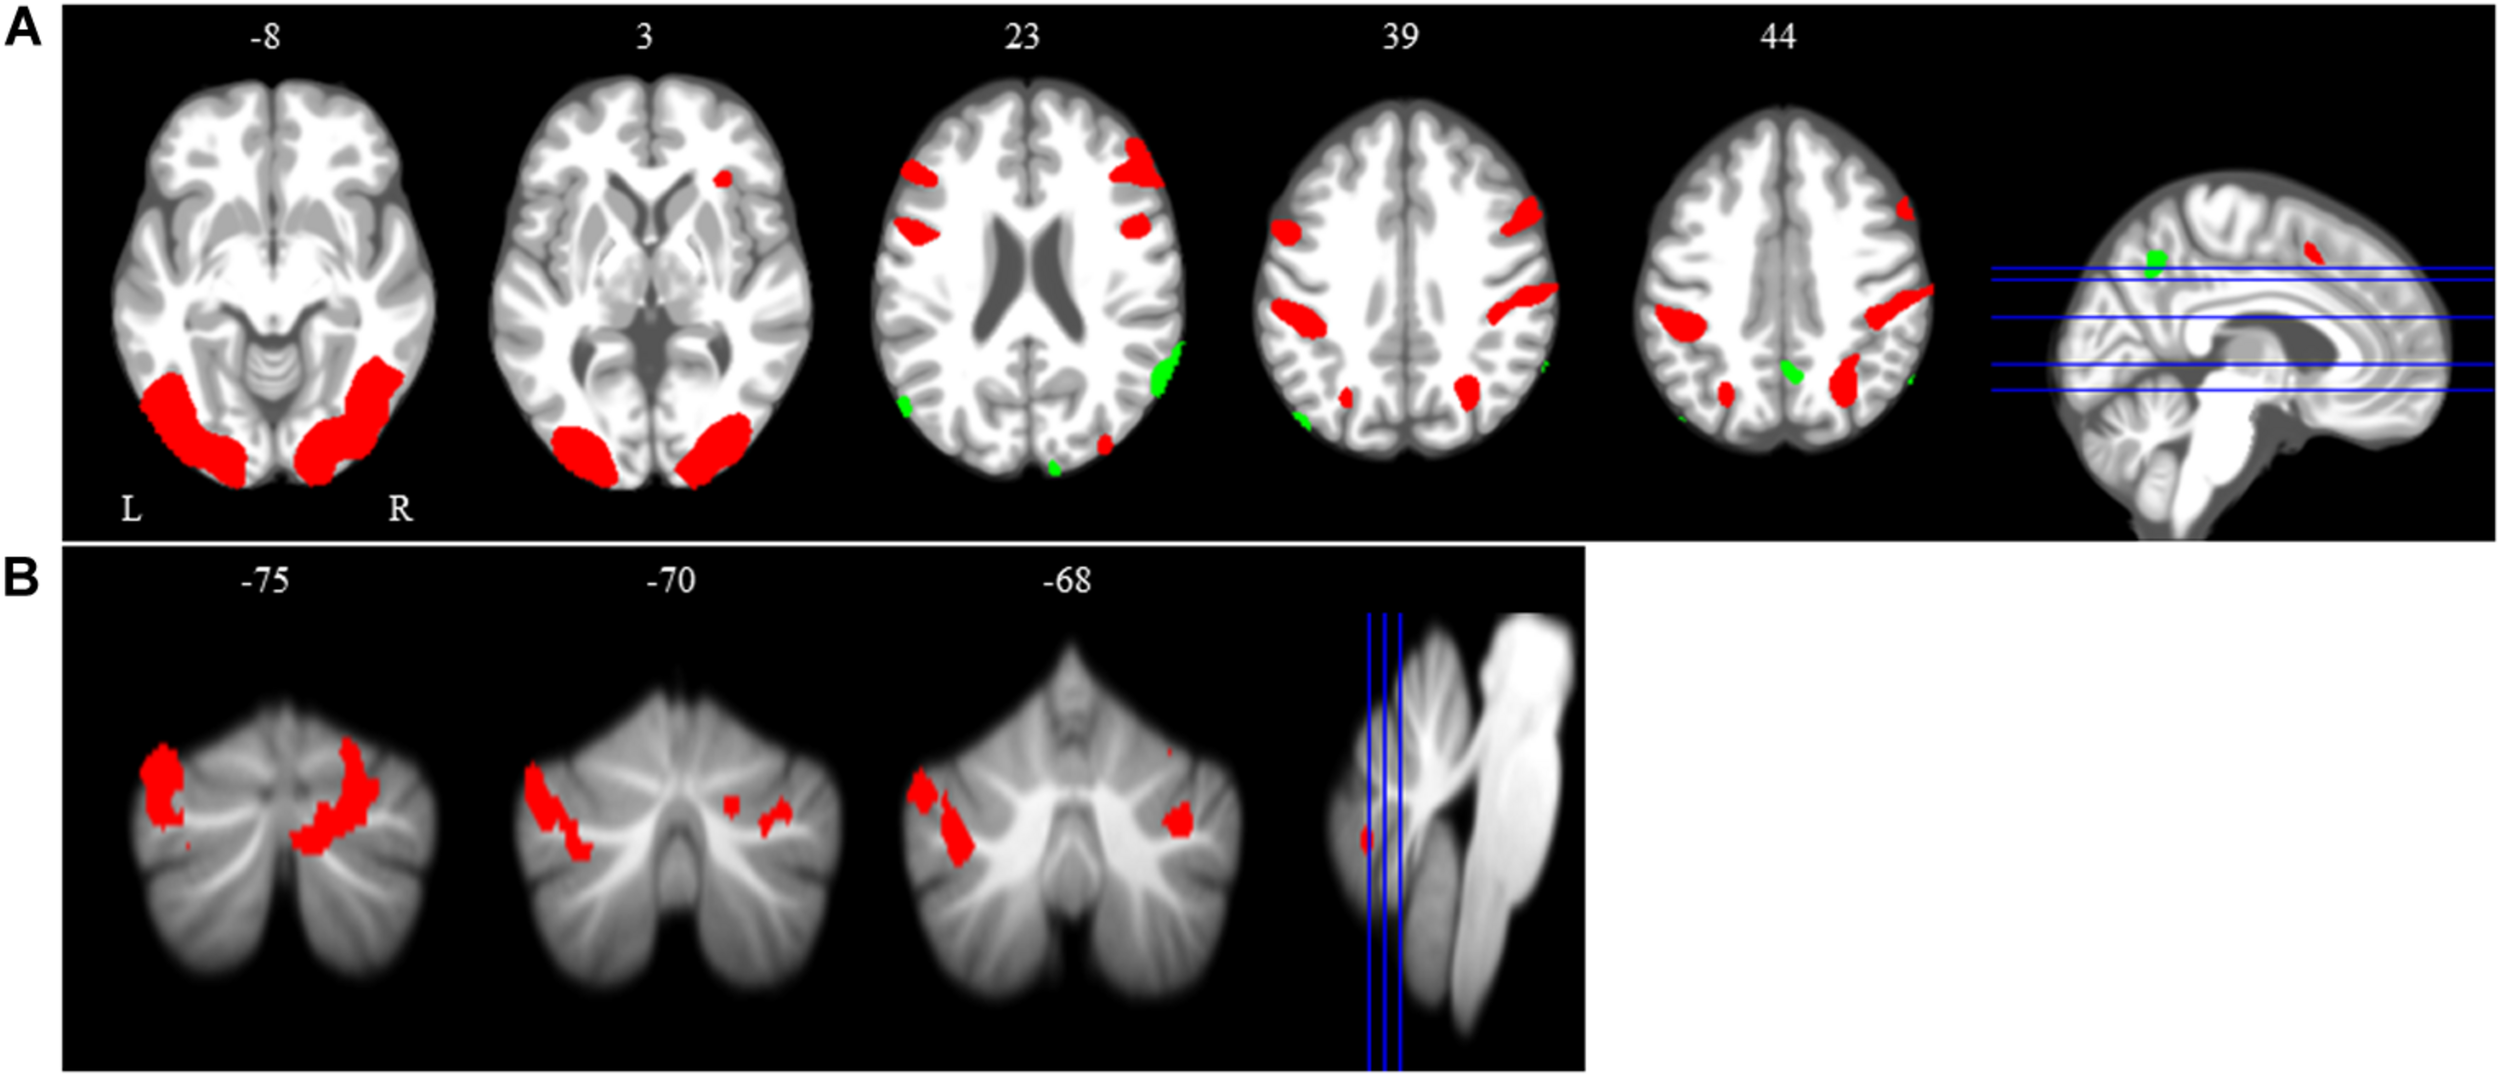

Main Effect of Spatial Working Memory

The main effect of the spatial working memory task contrasted to the control task resulted in activation in the expected brain regions based on prior studies (Lamp et al., 2016). Specifically, we observed bilateral activation in several frontal, parietal, temporal and cerebellar regions (Table 1 and Figure 4). We also found deactivation in parietal and occipital regions (Table 1 and Figure 4).

Figure 4. Main effect of spatial working memory. The spatial working memory task resulted in widespread activation (red) and deactivation (green). Whole brain and cerebellar results are overlaid onto MNI (A) and SUIT (B) standard templates, respectively; p < 0.001, k = 10. Abbreviations: L = Left; R = Right.

Time Course of Neural Working Memory Response to HDBR + CO2

Across HDBR + CO2, we found decreasing activation in the right middle frontal gyrus and left dentate nucleus of the cerebellum, followed by recovery after the HDBR + CO2 intervention (Figure 5 and Table 2). We did not observe any increases in brain activation followed by recovery in response to HDBR + CO2.

Figure 5. Time course of neural spatial working memory response to HDBR + CO2. Whole brain and cerebellar results showing decreases in activation (green) followed by recovery. Whole brain and cerebellar results are overlaid onto MNI (A) and SUIT (B) standard templates, respectively; p < 0.0005, k = 10 for whole brain analyses; k = 5 for cerebellar analyses. Abbreviations: L = Left; R = Right.